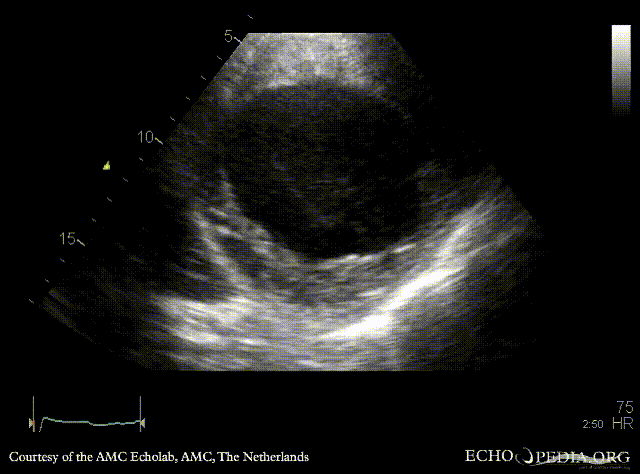

E00221.gif

A2CH: cardiac aneurysm